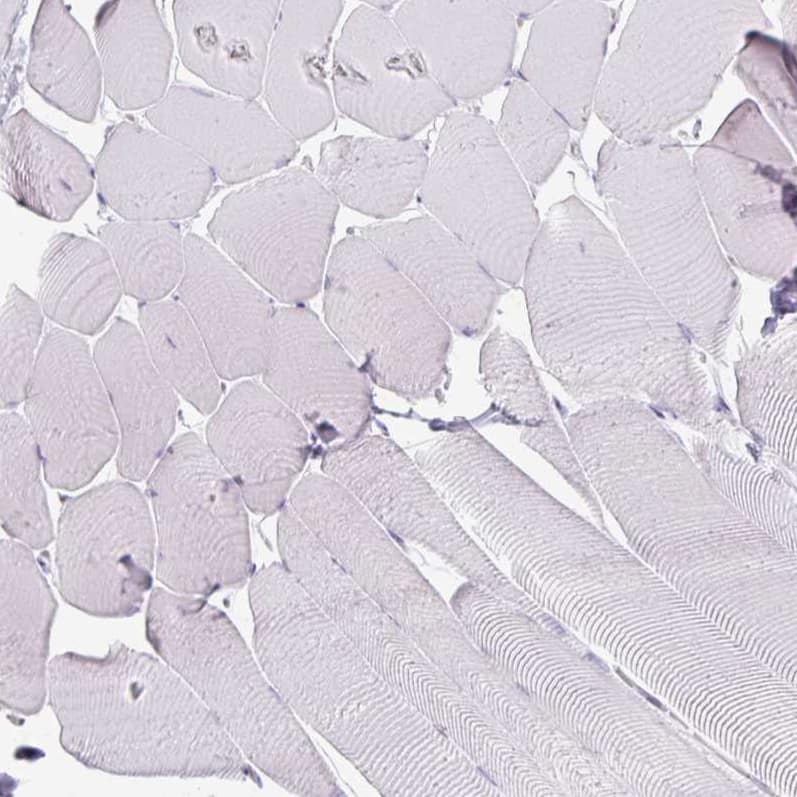

Orthogonal Strategies: Analysis in human liver and skeletal muscle tissues using NBP3-44441 antibody. Corresponding Arginase 1/ARG1/liver Arginase RNA-seq data are presented for the same tissues.

Staining of human skeletal muscle shows no positivity in myocytes as expected.